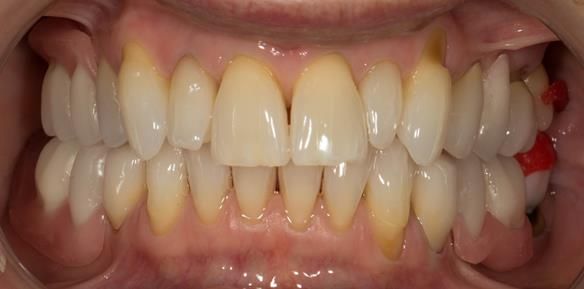

This newsletter describes in step by step detail Angela's transition through immediate partial dentures to crown supported definitive metal based dentures.

This 58 year old woman was referred to me by her general dental practitoner for treatment.

- Generalised Periodontitis; Stage 4, Grade C, Currently Unstable. Risk Factors: Type 1 diabetes. 16, 17 - hopeless prognosis. 14, 24, 26, 27, 34, 37, 44 - guarded prognosis

- Poor marginal fit and poor appearance of crowns and bridgework

- Yellowing teeth

The clinical situation and treatment process is shown in detail below with photographs. I (Finlay Sutton) provided the clinical work and Rowan Garstang provided the technical work.